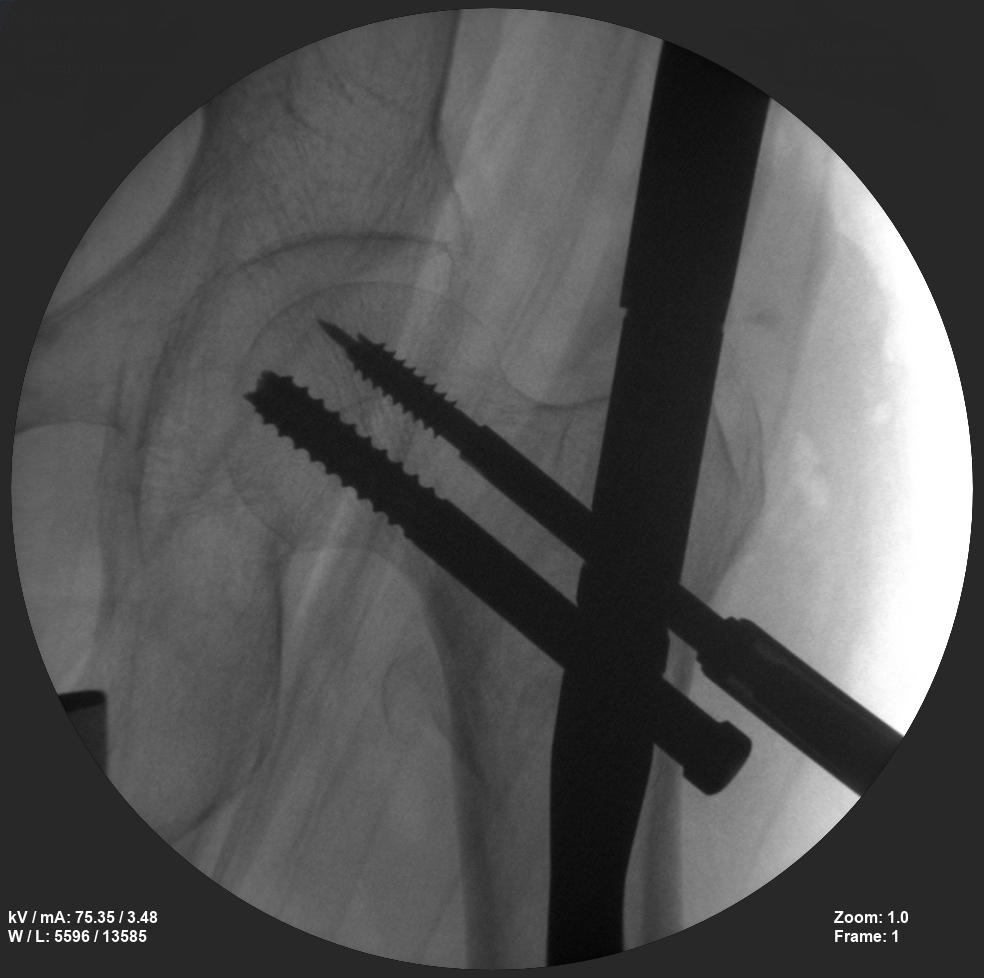

ORIF - Open reduction internal fixation

Skan-C is a great C-arm for orthopaedic treatments for several reasons